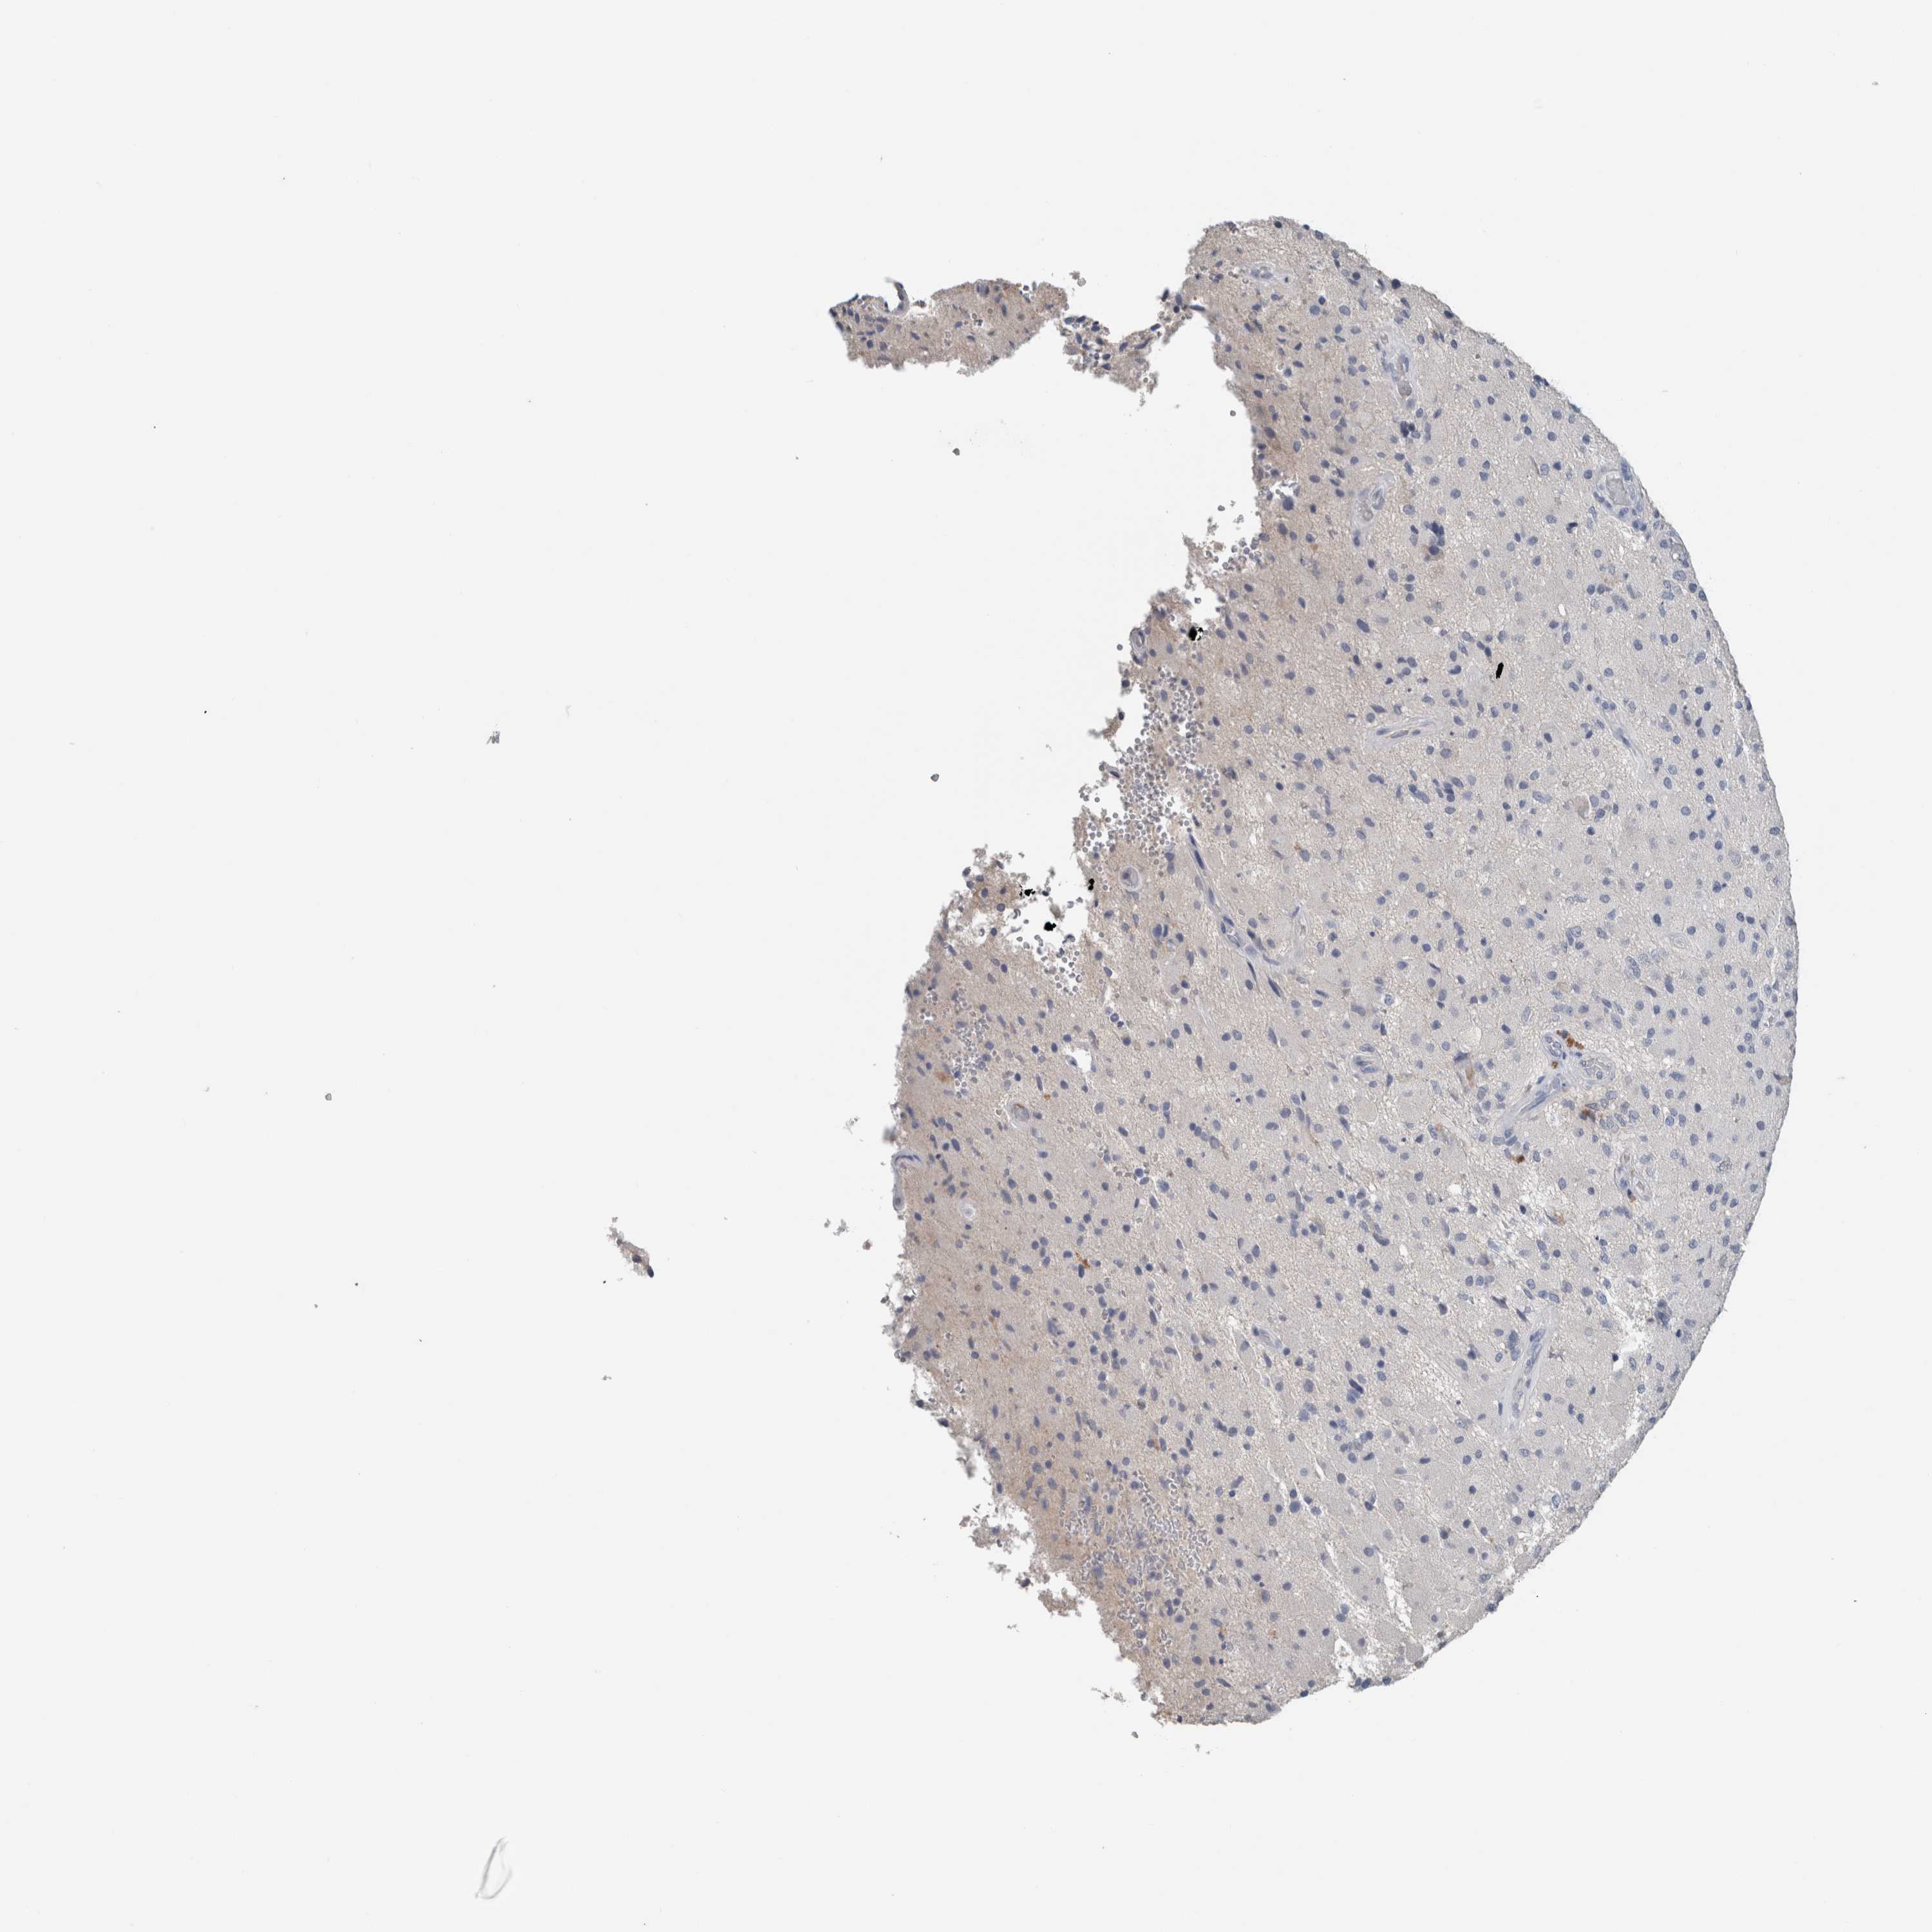

GLIOMA - Protein expressioni

A mouse-over function shows sample information and annotation data. Click on an image to view it in a full screen mode. Samples can be filtered based on level of antibody staining by selecting one or several of the following categories: high, medium, low and not detected. The assay and annotation is described here.

Antibody stainingi

Antibody staining in the annotated cell types in the current human tissue is reported as not detected, low, medium, or high, based on conventional immunohistochemistry profiling in selected tissues. This score is based on the combination of the staining intensity and fraction of stained cells.

Each image is clickable and will lead to virtual microscopy that enables deeper exploration of all samples and also displays staining intensity scores, fraction scores and subcellular localization as well as patient and tissue information for each sample.

Antibody HPA024343

Antibody CAB026182

Staining

High

Medium

Low

Not detected

Intensity

Strong

Moderate

Weak

Negative

Quantity

>75%

75%-25%

<25%

None

Location

Nuclear

Cytoplasmic/membranous

Cytoplasmic/membranous,nuclear

Glioma, malignant, High grade

Glioma, malignant, Low grade